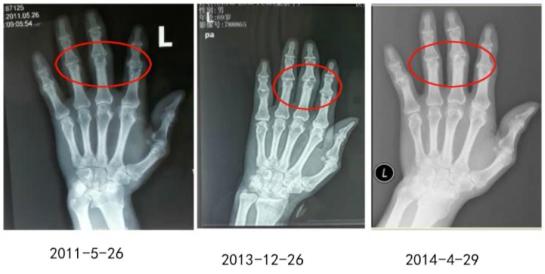

图3:患者手关节、膝关节和脚关节的变化

图4:影像学检查苏茵主任提示,虽然我们能够从11年到14年的影像学资料上看到,该患者近端指间关节处有明显的关节破坏,但这种破坏跟我们以往看到类风湿关节炎的虫噬样改变是不一样的。